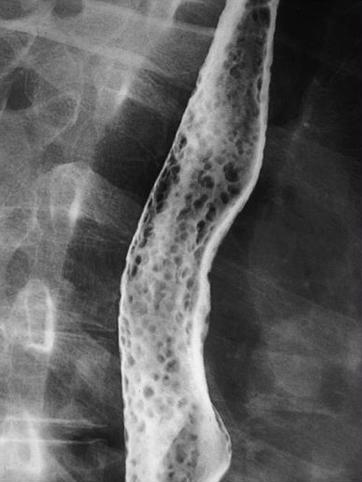

하지 동정맥 기형이 합병된 Cowden병의 1예

[Image-ID:10911]

종양양 병변/Cowden병

부위(장기별)

식도/2개 이상

검사방법

X-P

1~9